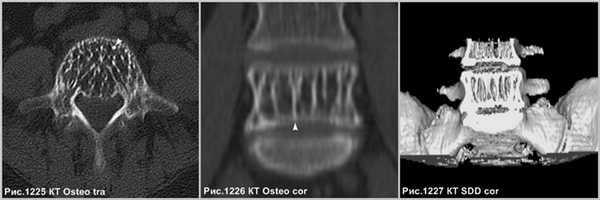

Гипертрофированные вертикальные балки губчатого вещества превосходно видны на КТ (рис.1227 и головки стрелок на рис.1225,1226).

Осложнение в развитии гемангиом в виде экспансивного роста, что встречается не часто, когда опухоль (звёздочки на рис.1228,1229) распространяется за пределы тела позвонка (головки стрелок на рис.1228,1229), приводит к компрессии спинного мозга (стрелки на рис.1228, 1229). Серьёзное осложнение представляет собой патологический перелом тела позвонка (головки стрелки на рис.1230), структура которого была ослаблена разряжением губчатого вещества в процессе роста гемангиомы.

В случае нахождения гемангиомы в дужке или распространения с тела в дужку позвонка (головки стрелок на рис.1231-1233), важно указывать данный факт в связи с тем, что структура позвонка в указанном месте ослаблена и может послужить причиной патологического перелома в процессе медицинских манипуляций, так же важно учитывать этот факт нейрохирургам при транспедикулярной фиксации.